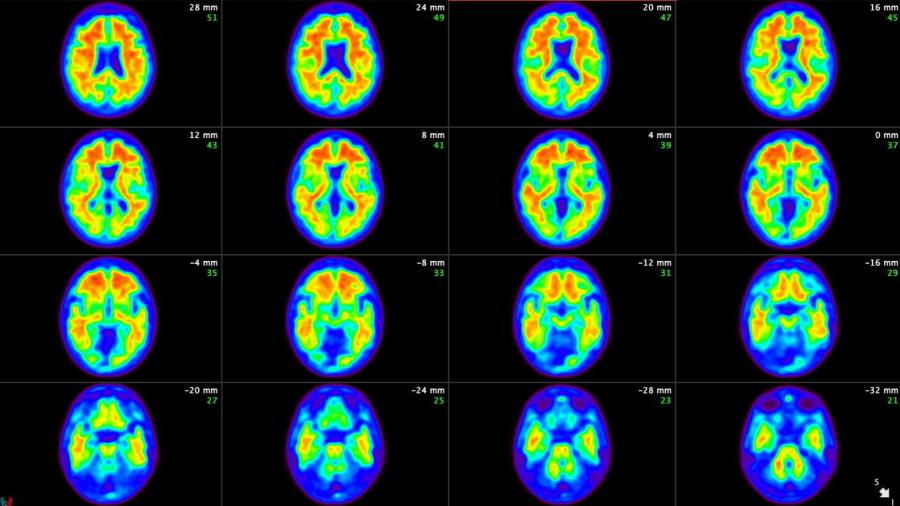

Both lecanemab and donanemab are based on antibodies against amyloid, one of the toxic proteins that build up in the brain as Alzheimer’s proceeds, but they worked at different stages of the process, Oakley said.

Lecanemab targets amyloid as it begins to form fibres in the brain while donanemab is active at a later stage, when the fibres have clumped together into larger accumulations of plaque. The main adverse side effect with both drugs was swelling and bleeding of the brain in a small minority of patients.

It cleared amyloid plaques completely from the brain in some participants, who were then taken off the drug.